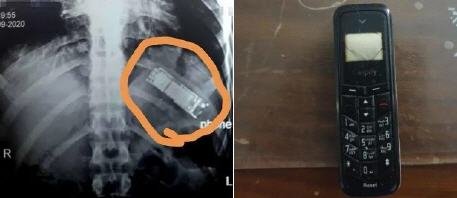

حادثة غريبة.. استخراج هاتف كان قد ابتلعه منذ 7 أشهر!

صباح الشرق / وكالات تمكن فريق طبي في مصر من استخراج هاتف محمول من معدة مواطن مصري كان قد...